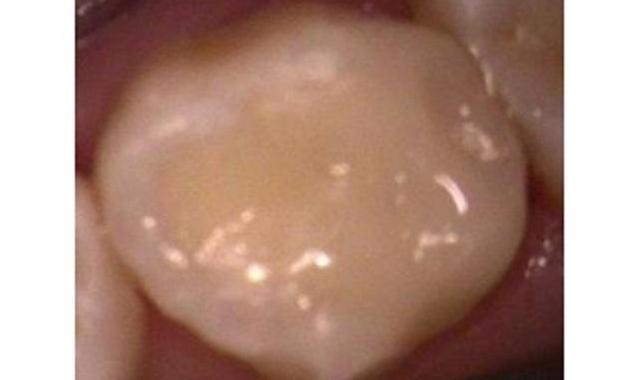

Smile Gallery: Tooth-Colored Dental Fillings

Before making a decision about any dental treatment, it's important to know that you're trusting your precious oral health and appearance to an experienced professional. Both Dr. Shahram and Dr. Sanati are passionate about delivering results that meet and exceed your expectations. Please take a look at the beautiful smiles of some of our patients and see for yourself!